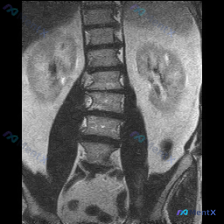

- 有一份腹部MRI-T2冠状位影像

- 影像科正式报告的结论是:双侧肾脏形态信号正常,未见腹腔积液及明确占位;腰椎椎体形态及信号未见明显异常

- 但观察者在看片时,直观觉得脊柱冠状面的排列“有点不对”,怀疑存在脊柱侧弯

目前没有提供患者的年龄、性别、症状或查体信息,也没有全脊柱影像。